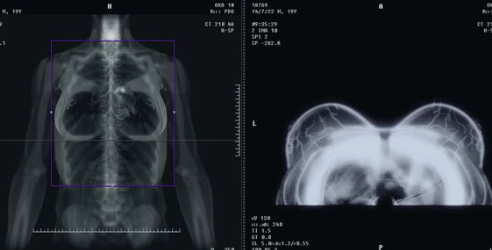

유방암은 조기 발견이 중요하기 때문에 정기적인 검진이 필요해요. 검진 방법에는 유방 촬영술, 초음파 검사, MRI 등이 있어요.

- 유방 촬영술 (Mammography): 유방을 압축해 촬영하는 방법으로, 미세한 종양을 발견하는 데 효과적이에요. 특히 40대 이상의 여성에게 권장돼요.

- 초음파 검사: 유방 조직이 치밀해 촬영술로 구분이 어려울 때 초음파 검사가 도움이 돼요. 30대 이상의 여성도 추천됩니다.

- MRI: 유방암 가족력이 있거나 고위험군에 해당하는 여성에게는 MRI 검사가 유용해요. 더 정밀하게 종양의 위치와 크기를 확인할 수 있어요.